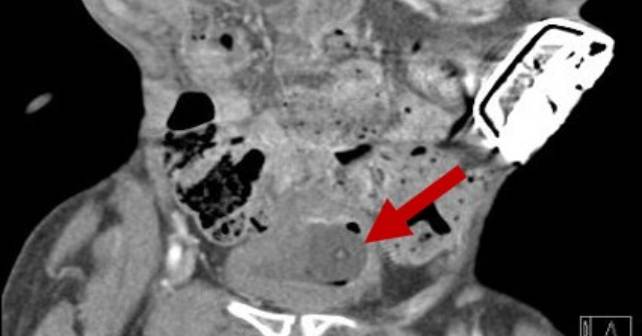

A CT abdomen and pelvis with contrast was obtained on the third visit revealing hydroureter and hydronephrosis with signs of pyelonephritis related to ureteral obstruction from the Foley catheter. At this presentation, the patient demonstrated fever at 39.3 degrees Celsius, an elevated white blood cell count, and was toxic appearing. The patient was started on antibiotics covering Klebsiella species (grown from urine culture obtained during the first visit) and the SPC was immediately replaced with confirmation of placement into the bladder with ultrasound. Intravenous fluids, blood cultures, and repeat laboratory evaluation were performed. There was no significant kidney injury; the patient remained hemodynamically stable and was admitted to the medical service.

Bladder indwelling catheters (BICs) carry a significant risk for injury and infection. The most common complications are urethral trauma and catheter-associated urinary tract infections. Placement of an SPC is more complex, and places patients at risk for complications not seen with BICs. More common complications include abdominal organ injury, hematuria, spasms, and stone formation, with a mortality risk of up to 2.4 percent.1,2 Rare yet severe complications may also occur including ureteral obstruction, ureteral rupture, and bladder prolapse. Many of these complications have limited support on proper management due to their low prevalence. There are only 35 known cases of accidental placement in the ureter (27 from BIC, 8 from SPC), with no significant difference with respect to laterality.3 There have also been case reports of the catheter balloon being inflated in the ureter causing ureteral rupture requiring urgent operative intervention.3 Luckily, in the case of our patient, the SPC had a longer tip, and the balloon was still in the bladder when inflated.